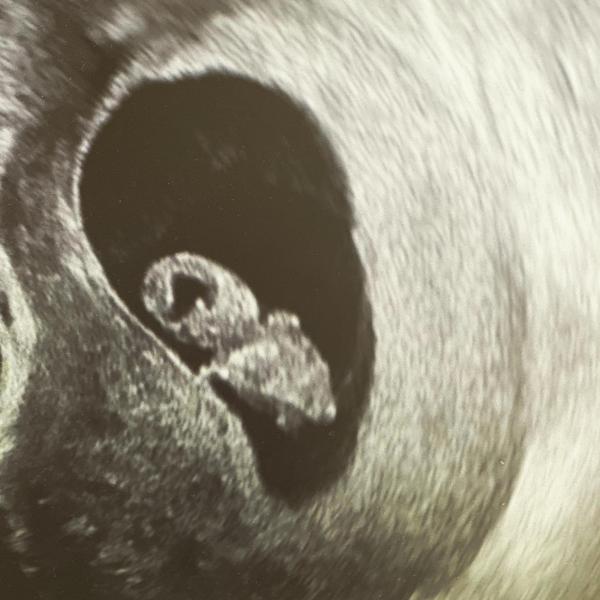

@fialka444 6+6 🙂 plod už vidět, 3mm, srdeční akce přítomna